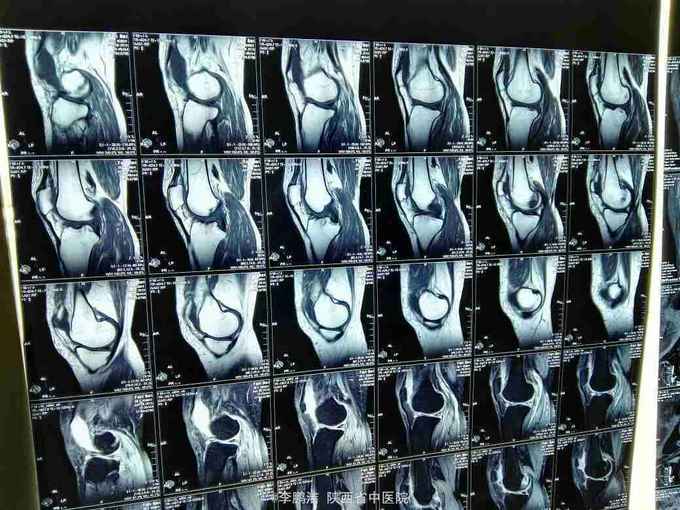

主诉:双膝关节疼痛,间断发作4年余。 现病史:患者于入院4年前因劳累后出现双膝关节疼痛,久行及上下楼梯时疼痛加剧,经休息疼痛好转,故当时未能引起重视,未进行系统治疗。其后因疼痛在当地诊所行局部理疗(具体治疗不详),经治疗后疼痛当时好转。之后,双膝关节疼痛症状时轻时重,间断性发作。近来,双膝关节疼痛症状加重,患者为求进一步治疗,遂于今日来我院就诊,门诊以“膝骨关节病”之诊断收住我科。

查体:脊柱生理弯曲尚可,L3-S1棘突及椎旁无压痛,双膝关节无肿胀,局部皮肤温度不高,内外侧副韧带止点压痛(+),髌韧带止点处压痛(-),鹅足滑囊处压痛(+),浮髌试验(-),髌骨摩擦试验(+),抽屉试验(-),双膝关节活动度明显受限;生理反射存在,病理反射未引出。

中医诊断:骨痹症 气滞血瘀 西医诊断:1、膝骨关节病 2、2型糖尿病 3、高血压 中医治疗方案:中药封包治疗、穴位贴敷舒筋通络。 西医治疗方案:口服阿托伐他汀钙片降脂,盐酸二甲双胍片、阿卡波糖片降糖,苯磺酸左旋氨氯地平片降压,硫酸氨基葡萄糖胶囊保护软骨面;患者夜间出现胸闷、气短,可行动态心电图、活动平板试验排除心脏疾病。 可给予口服活血化瘀,行气宽中之中药汤剂,具体方剂如下: 生地黄25g 当归10g 川芎15g 桃仁10g 红花10g 赤芍15g 柴胡10g 枳壳10g 怀牛膝15g 桔梗10g 生甘草6g 黄连10g 半夏(清半夏)15g 瓜萎15g 山栀10 7付水煎服 一日一剂